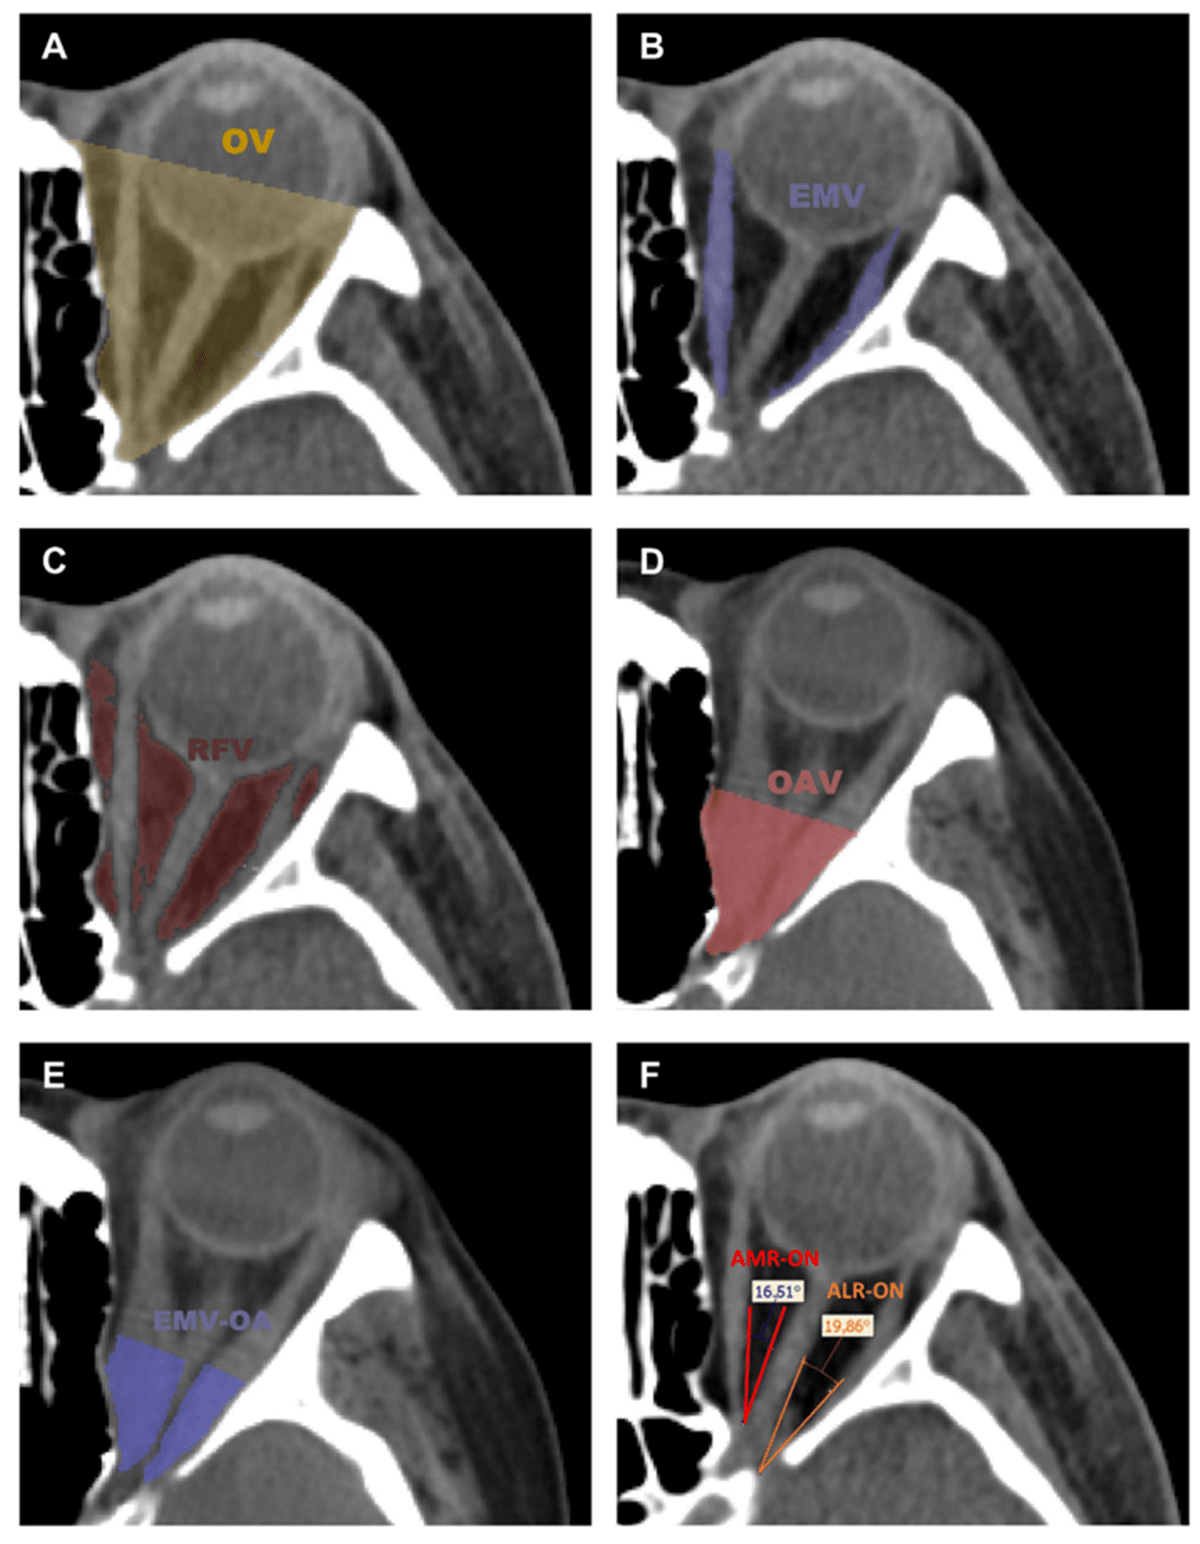

Parameter measurements include orbital volume (OV), extraocular muscle volume (EMV), retroorbital fat volume (RFV), orbital apex volume (OAV), extraocular muscle volume in orbital apex (EMV-OA), the angles between medial rectus and optic nerve (AMR-ON), and the angle between the lateral rectus and optic nerve (ALR-ON) . The extraocular muscles include four muscles as follows: medial rectus, lateral rectus, superior rectus, and inferior rectus.

Axial CT slices with the highlighted segmented tissues. (A) orbital volume (OV), (B) extraocular muscle volume (EMV), (C) retroorbital fat volume (RFV), (D) orbital apex volume (OAV), (E) extraocular muscle volume in orbital apex (EMV-OA), (F) the angle between the medial rectus and optic nerve (AMR-ON), and the angle between the lateral rectus and optic nerve (ALR-ON).